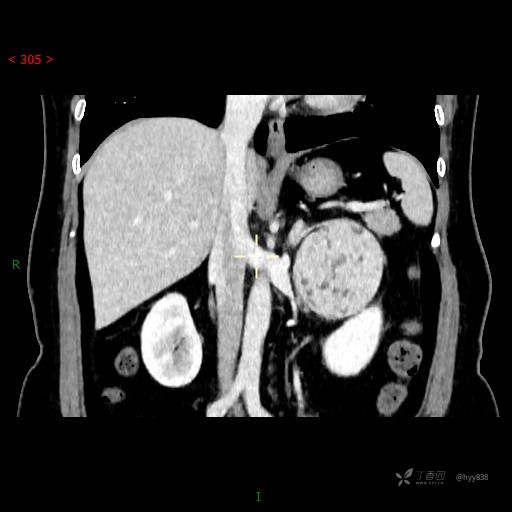

中腹部CT平扫

增强动脉期

增强静脉期